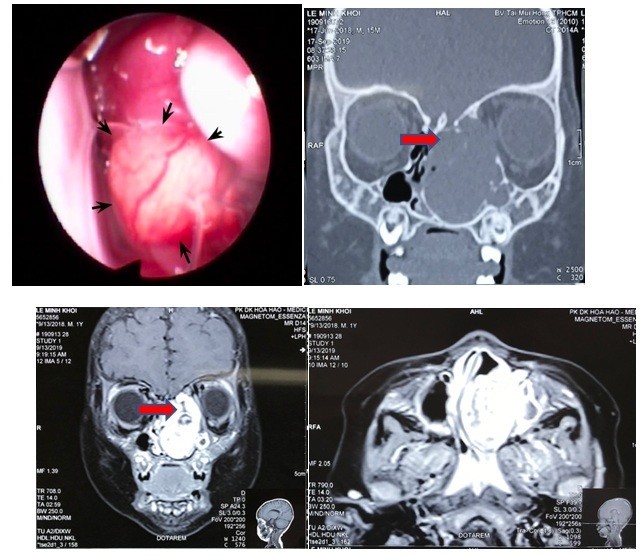

Hình ảnh nội soi và CT scan khối u lớn vùng hốc mũi trái. Ảnh: BVCC |

Tại BV Tai Mũi Họng TP.HCM, bác sĩ tiến hành các xét nghiệm và đã chẩn đoán vùng hốc mũi trái của bé có khối u kích thước khoảng 35mm. Khối u này gây biến dạng, hủy xương sàng, xương thành trong hốc mắt và một phần mềm sọ, đồng thời, khối u đè ép các cấu trúc hốc mũi, chèn ép đỉnh hốc mắt và hậu nhãn bên trái.

Đây là trường hợp khó do khối u nằm ở sát nền sọ nên nguy cơ chảy dịch não tủy trong lúc phẫu thuật là rất cao.